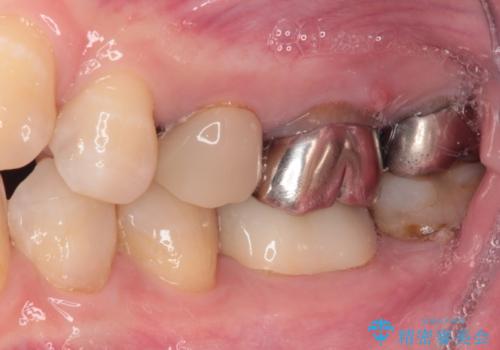

むし歯で神経を取り除いたことをきっかけに、前歯をセラミックにしたそうですが、金属の縁が見えてきたり、内側に引っ込んでいた歯を強引に前に出しことで汚れが溜まったりと、不具合を感じているとのことでした。

また、奥歯にも痛みがあったり治療途中で放置されていたりと、全顎的な治療が必要な状況でした。

その後、奥歯は痛みのある部分から少しずつ、根管治療やインプラント治療などを行うこととしました。